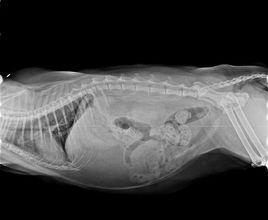

病貓的表現是精神沉鬱,食慾減退或廢絕,咳嗽,體溫高達40-C以上,鼻液初為漿液性,後期轉為灰白膿性鼻涕。貓肺炎最為顯著的特徵是呼吸困難,呼吸次數加快,呼吸的胸壁運動變淺表。當肺部進一步發生病變時,呈現進行性呼吸困難,病貓就明顯張口呼吸,還不時有短速的深咳,口鼻呈深紫色。肺部聽診時,可聽到羅音 支氣管呼吸音等異常的聲音。X射線檢查時,可見炎症部位呈現陰影,似雲霧狀,大小不等,甚至擴散融成一片。